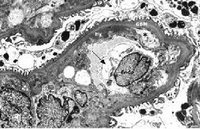

妊娠晚期及分娩期,孕婦凝血功能明顯增強,血液處於高凝狀態,有助於防止分娩及產後大量出血,這是由多種因素引起的止血、凝血和抗凝系統改變的一種複雜的生理過程,妊娠子癇前期是一種嚴重的、多臟器功能受損的妊娠併發症,其病理過程包括全身小血管痙攣、血管內皮細胞損傷、凝血/纖溶系統活性失衡、血小板激活,微血管內血小板聚集和血栓形成。